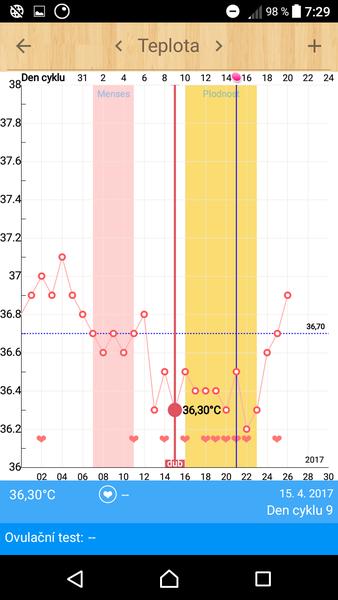

Těhotenský test. Dávám fotku. Co myslíte?

dnes jsem si dělala testík...

Jinak melo by to byt 9dpo, 10dpo a dnešní spodní 11dpo mozna o den min, uplne si nejsem ze dvou dni jistá který byla ovulace.. ms nema dorazit v sobotu